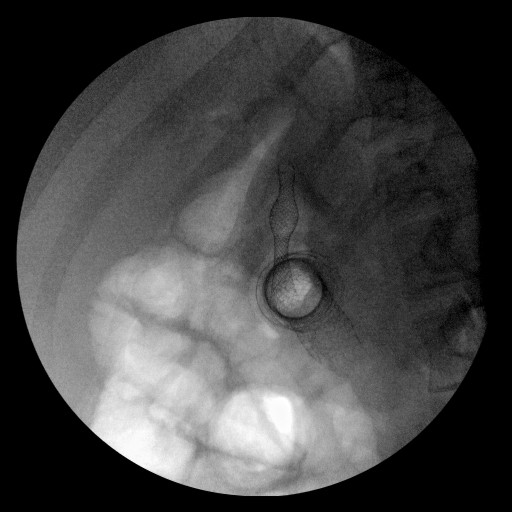

Thus, EUS-guided transduodenal biliary drainage (EUSBD) was performed. A linear array echoendoscope (GF-UCT140, Olympus America, Center Valley, PA, USA) was placed in the duodenal bulb allowing visualization of a dilated common bile duct (Figure 1). A 19-gauge FNA needle (Wilson-Cook Endoscopy, Winston-Salem, NC, USA) was used to perform a transduodenal puncture of the common bile duct through the proximal end of the duodenal stent. Bile was aspirated and a cholangiogram demonstrated good filling of the right and left duct systems with no evidence of a stricture proximal to the puncture site (Figure 2). Under fluoroscopy, a 0.035-inch straight guidewire (Jagwire, Boston Scientific Corporation, Natick, MA, USA) was passed into the biliary tree and directed toward the hilum. The FNA needle was exchanged for a biliary dilating balloon (Hurricane RX, Boston Scientific Corporation, Natick, MA, USA). The choledochoduodenostomy tract was dilated to 6 mm. A 10x60 mm fully covered self-expanding metal biliary stent (Wallfex®, Boston Scientific Corporation, Natick, MA, USA) was placed over the guidewire and deployed under fluoroscopy. One cm of the stent was left protruding into the duodenal bulb through the mesh at the proximal end of the duodenal stent (Figure 3). Good bile and contrast efflux was seen. The final fluoroscopic image did not demonstrate a bile leak (Figure 4). Post-procedure CT imaging demonstrated good positioning of the biliary stent and no evidence of a bile leak (Figure 5).

Figure 4. Final fluoroscopic image of biliary and duodenal stents. |